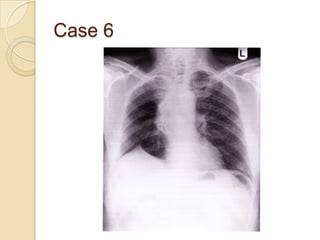

Case 6

   Right upper lobe

lobectomy

◦ Volume loss of right

lung

◦ Right tracheal

deviation

◦ Remaining right lung

hyperinflated, appea

rs darker

◦ Right diaphragm –

diagphragmatic

tenting

Case 6  Right upper lobe lobectomy ◦ Volume loss of right lung ◦ Right tracheal deviation ◦ Remaining right lung hyperinflated, appea rs darker ◦ Right diaphragm – diagphragmatic tenting